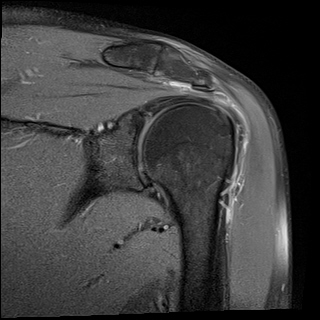

±Ø»ó°Ç ¿ÜÃø Á¾´Ü¸é°Ë»ç ½Ã Á¡¾×³¶ ºÎÁ¾ÀÌ °üÂûµÊ(±×¸² 4).

ŽÃËÀÚ¸¦ °ßºÀ ¿ÜÃø¿¡ ´ë°í ÆÈÀ» ¿ÜÀüÇϸ鼭 ´ë°áÀý°ú °ßºÀÀÇ Ãæµ¹À» °üÂûÇÏ´Ï °ßºÀ¿ÜÃø¿¡

¼ö¾×ÀÌ Àú·ùµÇ¾î ¿ÜÃø Ãæµ¹ÁõÈıºÀÌ È®ÀεǾú´Ù(÷ºÎ ÆÄÀÏ 1).